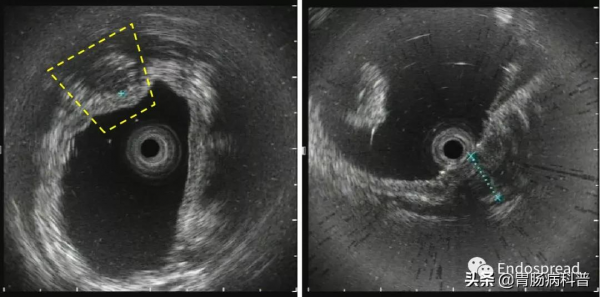

超聲內鏡見黏膜層增厚為主但累及黏膜下層,低迴聲為主但病變不均勻,似可見無回聲區,固有肌層連續完整,長徑17mm(圖3)。

圖3 超聲腸鏡觀察病變